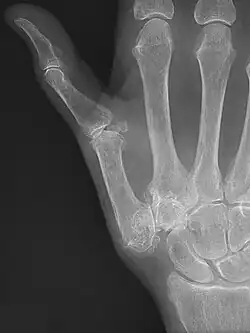

TMC OA is diagnosed based on symptoms and signs.[8] Radiographs can confirm the diagnosis and the severity of TMC OA. Other diagnoses in this region include scaphotrapezial trapezoid arthritis and first dorsal compartment tendinopathy (De Quervain syndrome) although these are usually easy to distinguish.

TMC OA severity was classified by Eaton and Littler which can be simplified as follows:[21][22]

Stage 1:

- slight widening of the joint space

- < 1/3 subluxation of the joint (in any projection)

Stage 2:

- Osteophytes, < 2 mm in diameter, are present. (usually adjacent to the volar or dorsal facets of the trapezium)

Stage 3:

- Osteophytes, > 2 mm in diameter, are present (usually adjacent to the volar and dorsal facets of the trapezium)

- Slight joint space narrowing

Stage 4:

- Narrow joint space

- Concomitant scaphotrapezial arthritis

A simpler classification is no arthritis, some arthritis, and severe arthritis.[23] This simpler classification system omits the potentially contradictory details of the Eaton/Littler classification and keeps scaphotrapezial arthrosis separate.